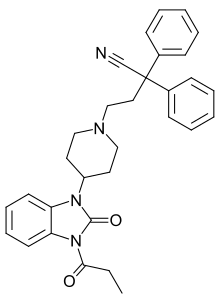

Anilidopiperidines

Benzimidazoles

Benzimidazoles opioids are also known as nitazenes.